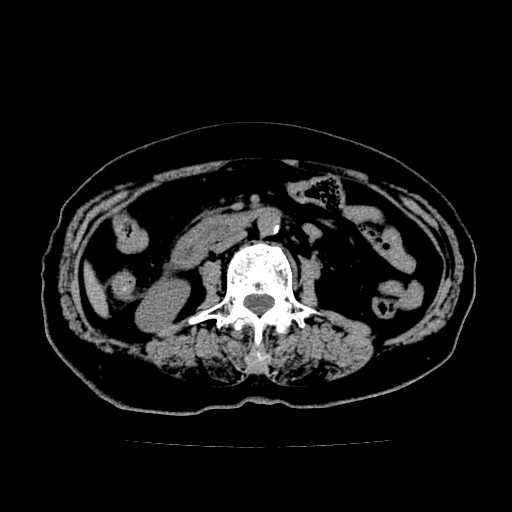

以下是引用lujiandong在2009-2-8 9:37:00的发言:[br]从所发的ct平扫图象上看,胆总管明显增粗,从上向下逐渐变细,是否有泥沙样结石,建议薄层重建;胰腺形态基本正常,左侧肾前筋膜轻度增厚。可以考虑:轻度单纯性胰腺炎,建议ct增强扫描。